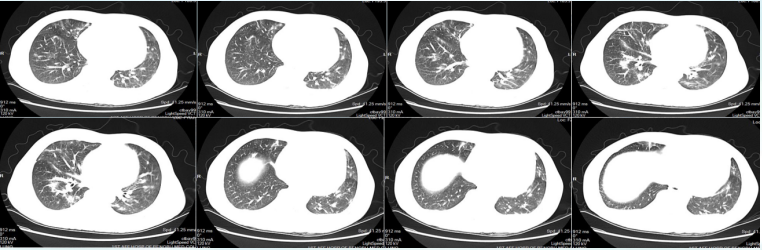

2022年4月25日(D7),患者尿量恢复,撤离CRRT。4月26日(D8),撤机拔管,序贯高流量氧疗。4月27日复查胸部HRCT示:病灶较前明显吸收(图15)4月30日(D12),病情好转出院。嘱托:口服复方磺胺甲噁唑0.96 g q8h维持治疗1年。

15  复查胸部HRCT(2022-04-27)